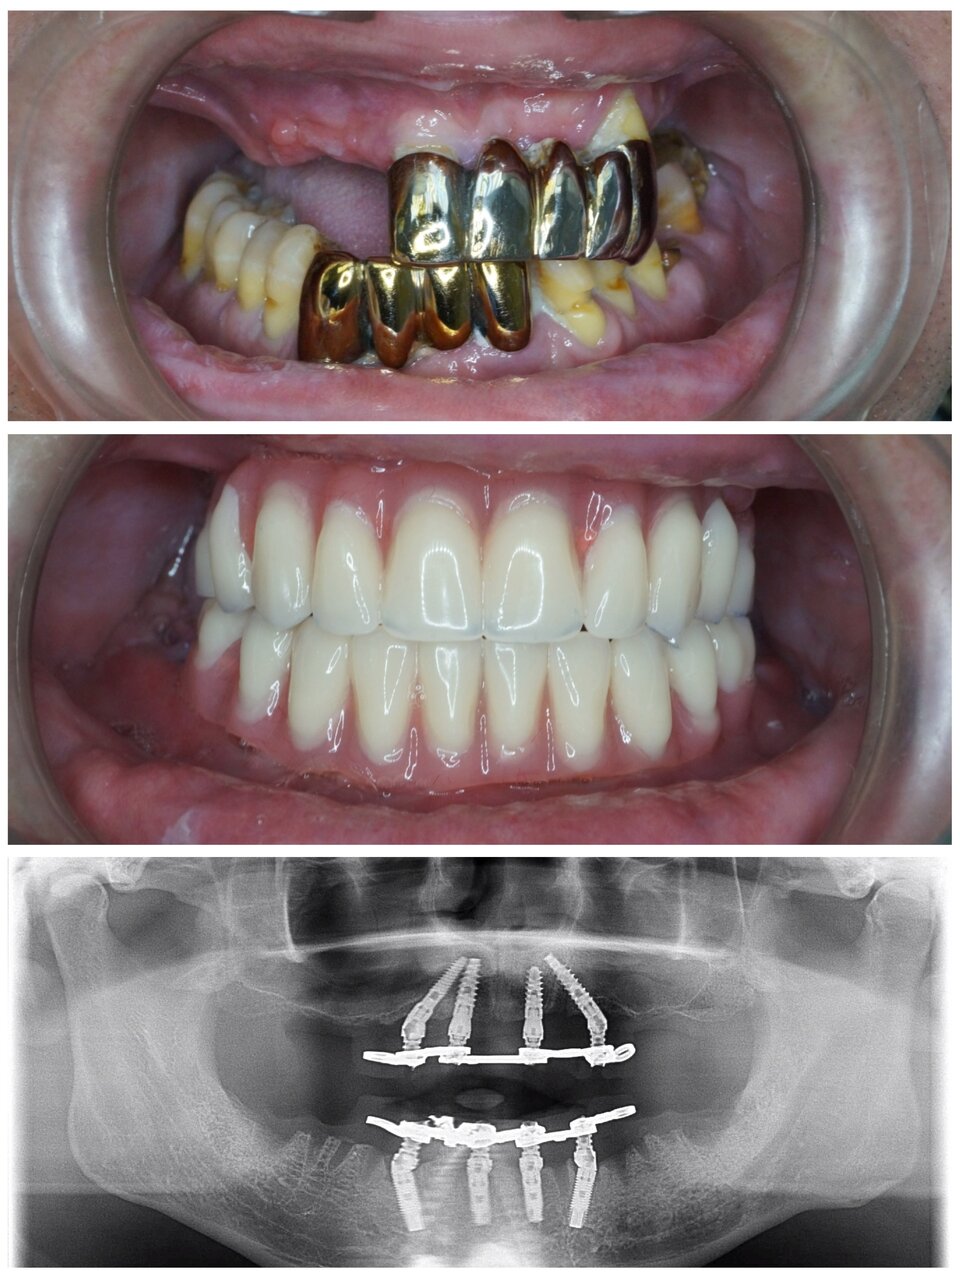

В клинике работают квалифицированные специалисты, включая стоматологов, ортодонтов, ортопедов и имплантологов. Основные направления деятельности включают терапию, хирургию, эстетическую стоматологию, протезирование, имплантацию, ортодонтическое лечение и гигиену полости рта. Среди дополнительных услуг доступны рентгенография, компьютерная томография, лечение под микроскопом, костная пластика, а также современные методы цифровой стоматологии CAD/CAM.

- протезирование

- коронки

- Положительные отзывы о протезировании (коронки, мосты, импланты).